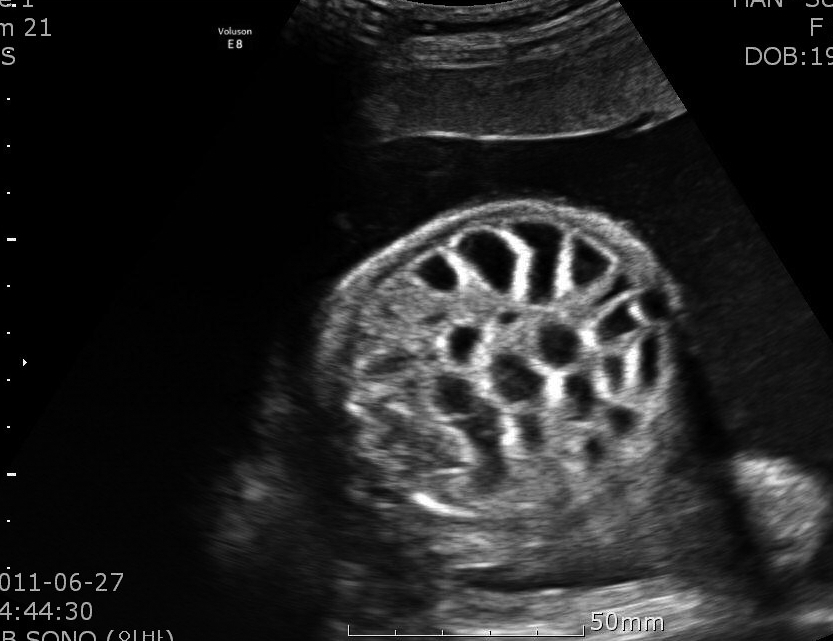

あと便中電解質を利用するのが遺伝性塩素下痢(congenital chloride diarrhea, CCD)だ。便Clが100mEq/l、あるいは便Clが便Naと便Kの和よりも高いときに診断が示唆される。といってもCCDは稀で基本的には胎児・新生児疾患(写真)だが、腎外性の代謝性アルカローシスの鑑別で教科書に載っているから一応知っておかなければならない。成人発症も、ほんとうに稀だがある(Am J Med 1988 85 570、Am J Gastoenterol 2007 102 1329)。